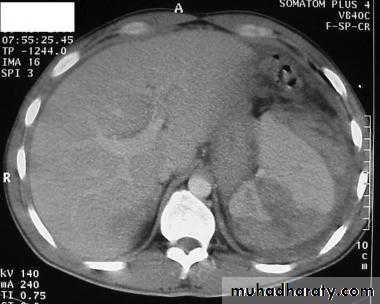

Spleen

CT

Splenic injurypancreas